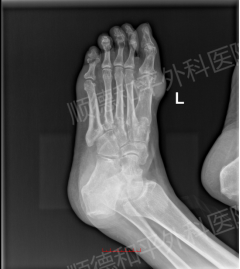

病例回顾: 患者林先生,年轻(33岁)但病史已达4年,痛风石已影响手指关键功能且造成外观困扰。手部结构精细,神经、血管、肌腱密布,对手术的精准度要求极高。

视野清晰放大: 在显微镜的高倍放大下,医生能清晰分辨出乳白色的尿酸盐结晶与正常的肌腱、韧带、神经组织,仿佛在“显微镜下挖土豆”。

精准彻底清除: 对于林先生手指关节内的痛风石,医生可以做到颗粒归仓式清除,不遗漏任何微小结晶。这不仅最大程度地解除了对神经、肌腱的压迫,恢复了手部精细功能,更从根源上减少了因残留尿酸盐结晶而导致的术后复发风险。同时,精准操作也保障了术后手部的美观性。